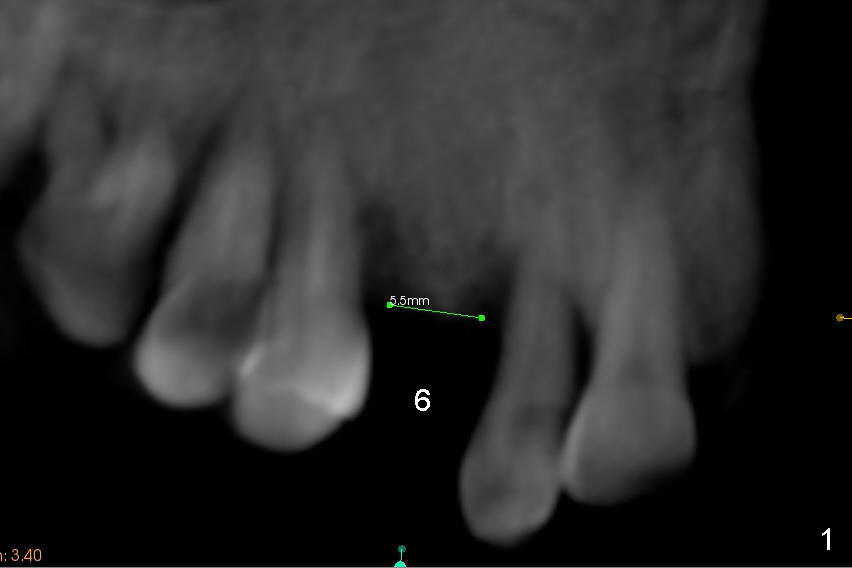

A 45-year-old lady has history of chronic periodontitis. The tooth #6 has lost several years (Fig.1). The buccolingual width decreases (Fig.2 (7mm), as compared to #11 in Fig.6 (10 mm)). Bone expansion is necessary for implantation. It should be done gently, since she is a dental phobic. First the crestal cortex is split with a surgical fissural bur (Fig.3 red line), followed by thin osteotomes (Fig.4 green line: scalpel, bone scalpels (probably until 5 or 6 mm, as indicated by Fig.1 (mesiodistal width)), bone blades (until 5.5 mm)). If the patient cannot tolerate tapping, 1.6 mm pilot drill is used at the depth of 14 mm, followed by bone expanders (probably until 2.9/3.8 using handpiece). As expanders or rounded osteotomes increases in diameter (Fig.5 green arrow), the buccal plate moves buccally (pink arrow). The bone expansion improves cosmetics as well. The implant is planned to be 4.5x14 mm, bone level. Angled abutment is expected. In contrast, immediate implant prevents buccal plate atrophy and avoids bone expansion. How is the surgery?